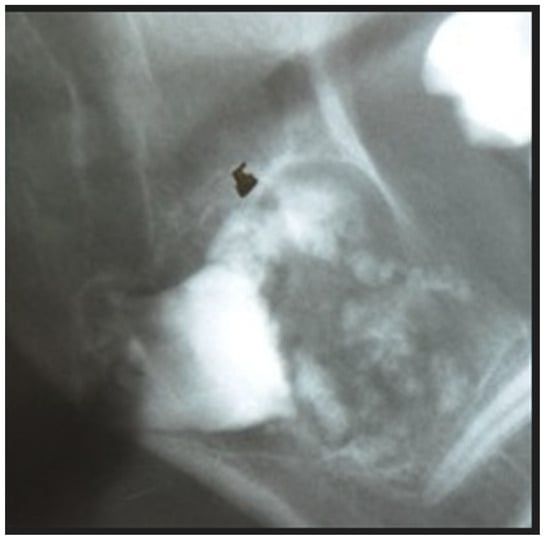

2. Case Report Presentation